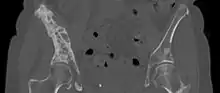

| 3D rendered CT scan of bone metastases of the hip bone, in a 60 year old woman with parotid gland cancer. Large lesions are seen on the ilium on the more distant side. Involvement of the vertebral column has caused a compression fracture. | |

CT Scan

A CT scan can detect bone metastases before they present with symptoms in patients diagnosed with tumors that are high-risk for spread to the bone. Even sclerotic bone metastases are generally less radiodense than enostoses, and it has been suggested that bone metastasis should be the favored diagnosis between the two for bone lesions lower than a cutoff of 1060 Hounsfield units (HU).[10] If a biopsy is indicated, a CT scan is often used to localize the lesion before biopsy.[14]